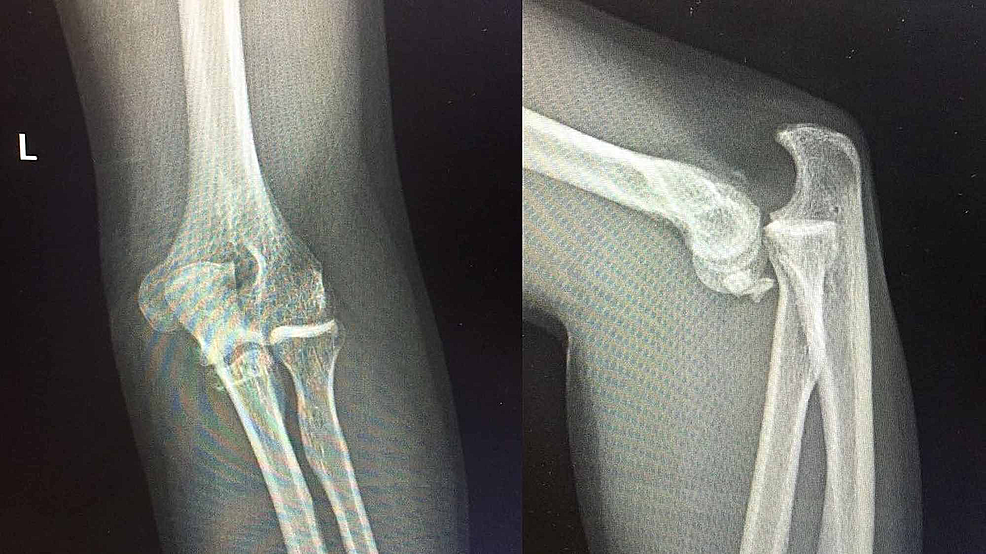

Xray Elbow Showing Fracture Proximal Ulna or Olecranon Fracture How Is Fractured Elbow Treated There are usually two treatments for elbow fractures depending on the fracture pattern, displacement and joint involvement. A splint or sling is used to hold the elbow in place during the healing process. Depending on the severity of the injury, nonsurgical and surgical options exist to help repair the broken bone. an elbow fracture should be diagnosed and treated. How Is Fractured Elbow Treated.

Xray Elbow Showing Fracture Proximal Ulna or Olecranon Fracture How Is Fractured Elbow Treated In most olecranon fractures, however, the pieces of bone move out of place when the injury occurs. simple fractures can be treated with a brief period of immobilization with a splint or sling followed by moving the elbow to pain tolerance. an elbow fracture should be diagnosed and treated by a medical professional. treatment depends on the. How Is Fractured Elbow Treated.